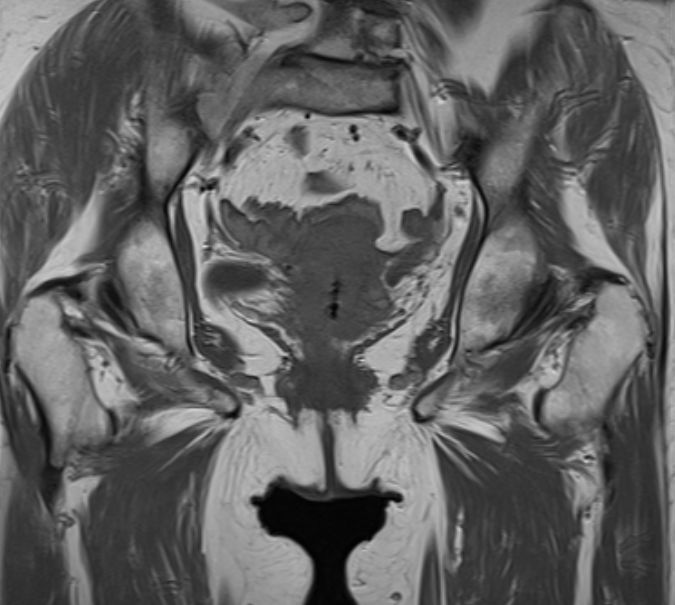

| MRT | 46-jährige Frau mit großem invasivem

Plattenepithelkarzinom der Zervix.![]() |

Im CT suspekter Lymphknoten iliaca externa links

neben der Blase.![]() | ||